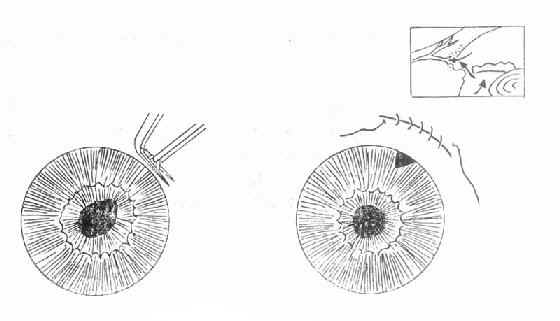

急性闭角型青光眼虽可用药物治疗使急性发作缓解,达到短期降压的目的,但不能防止再发。因此眼压下降后应根据病情,特别是前房角情况,尽快选择周边虹膜切除术或滤过性手术(图10-4)。

图10-4 周边虹膜切除术

若停药48小时眼压不回升,房角功能性小梁网1/2以上开放以及青光眼临床前期,可施行周边虹膜切除术。对于眼压控制不到正常范围,房角已发生广泛前粘连者,应考虑作滤过性手术或小梁切除术。(图10-5)。